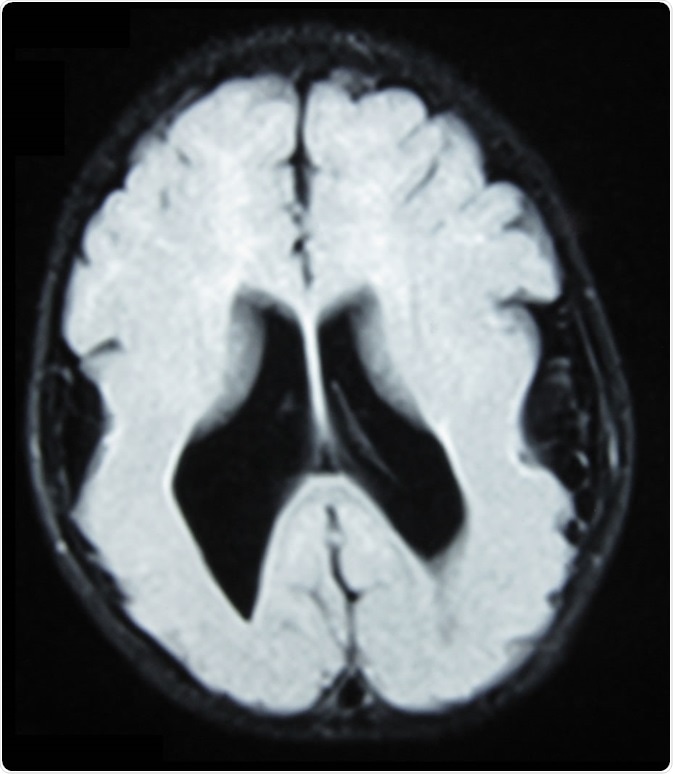

Brain MRI, T1 weighted, transverse plane, that shows lyssencephaly, manifested as scarce and wide circumvolutions, mostly in the occipital, parietal and temporal lobes. As aggregated findings, there is ventriculomegaly, no true Sylvian cissure, too thick gray matter and ectopic gray matter in the white matter. Image Credit: Ralphelg, https://creativecommons.org/licenses/by-sa/3.0/deed.en

Brain MRI, T1 weighted, transverse plane, that shows lissencephaly, manifested as scarce and wide circumvolutions, mostly in the occipital, parietal, and temporal lobes. As aggregated findings, there is ventriculomegaly, no true Sylvian cissure, too thick gray matter and ectopic gray matter in the white matter. Image Credit: Ralphelg, https://creativecommons.org/licenses/by-sa/3.0/deed.en